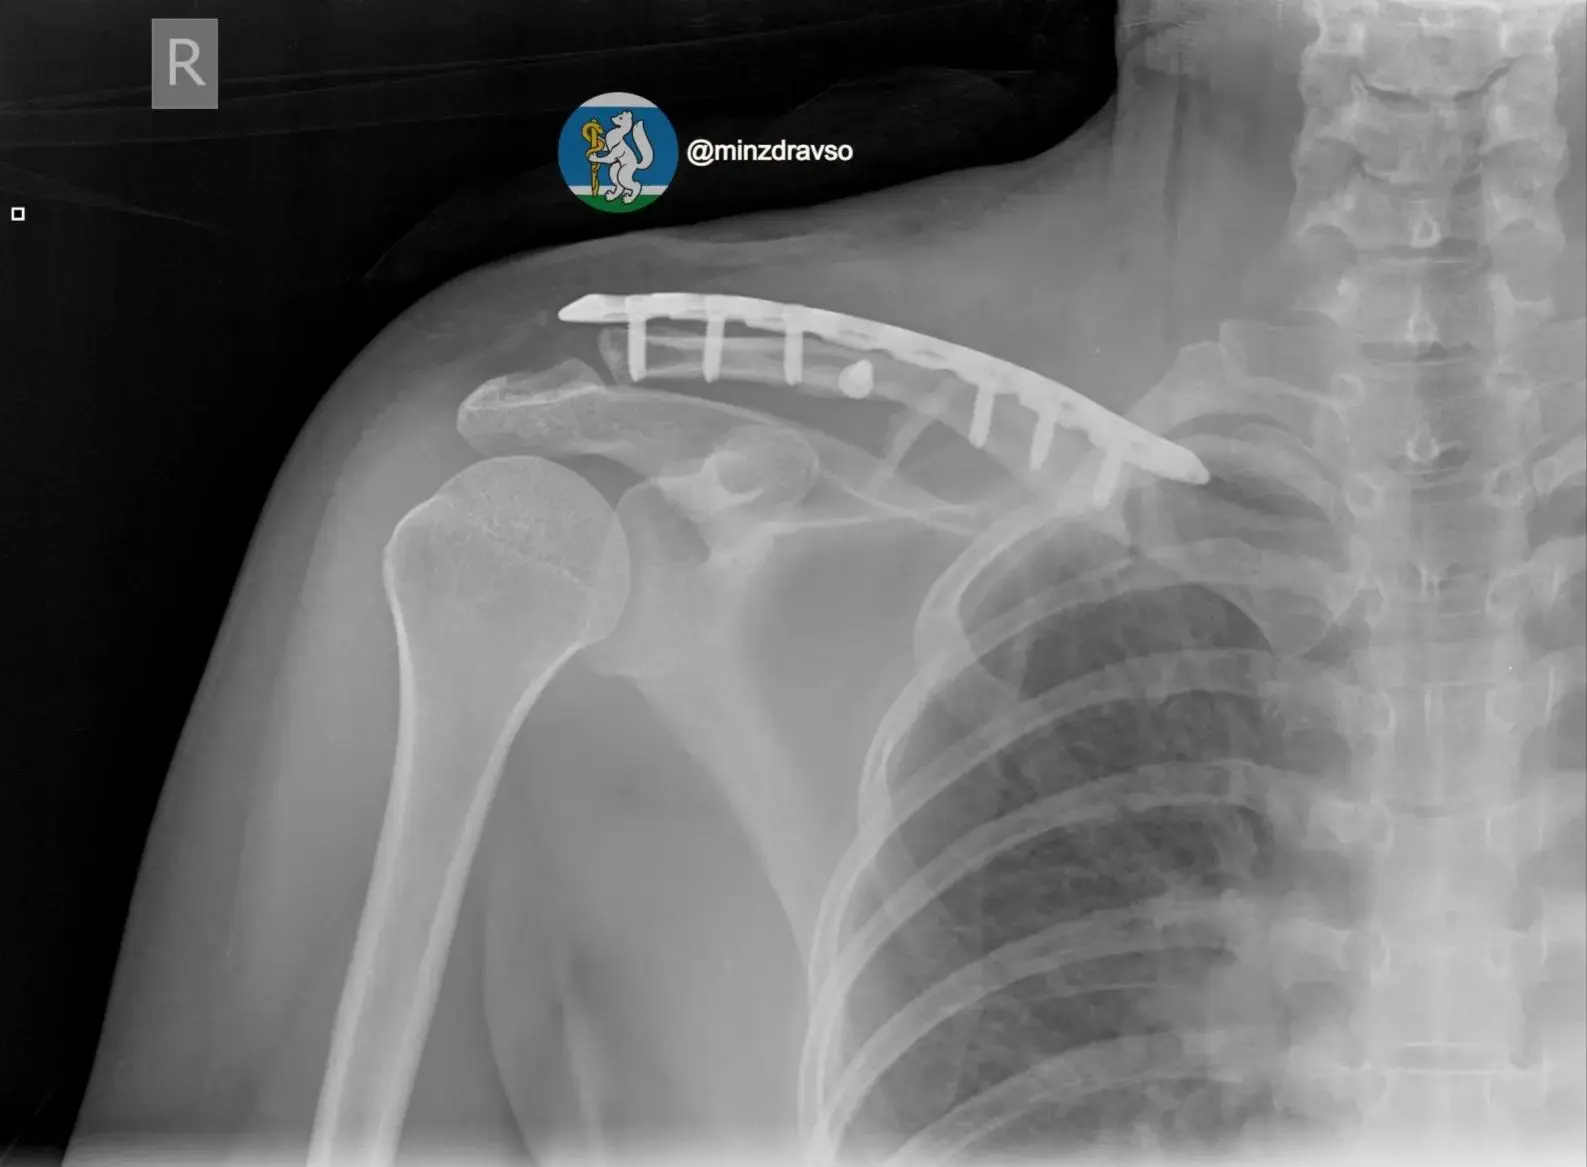

Врачи диагностировали тяжелую политравму, включающую закрытую черепно-мозговую травму, ушиб головного мозга, повреждение челюстно-лицевых костей, ребер, двусторонний пневмоторакс, оскольчатый перелом правой ключицы и раздробленные кости таза.